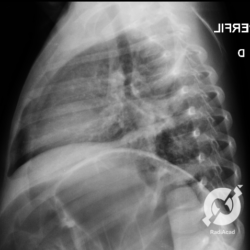

Os agentes etiológicos infecciosos são variados (bactérias, vírus, fungos, parasitas…), mas o que ocorre nos pulmões durante uma infecção por qualquer tipo de agente é a substituição do ar alveolar por secreção (pus, muco, eventualmente sangue ou necrose…) e com isso a manifestação radiográfica vai ser a mesma já que todas estas secreções apresentam a mesma densidade radiográfica: partes moles.

E o nome dado a esta alteração radiográfica que corresponde à substituição do ar alveolar por líquido é a consolidação alveolar.

Uma consolidação alveolar é, por definição, uma opacidade (imagem densa, branquinha) homogênea ou às vezes heterogênea (pela presença de calcificações ou cavidades), de limites mal definidos, exceto quando toca a pleura da parede ou das cissuras pulmonares. É um termo usado tanto em radiografia, como em tomografia computadorizada. Na tomografia, um outro termo é usado: vidro fosco, que é uma opacidade (branquinha mas não tanto como a consolidação), que borra o pulmão mas deixa ver os vasos de permeio (igual bigode de adolescente: dá pra ver todo o fundo).

Nós vamos mostrar aqui um pequeno apanhado de pneumonias de variados agentes, em diversos segmentos e lobos pulmonares, com extensões variadas. O objetivo é identificar o padrão radiológico de consolidação alveolar e não determinar o agente infeccioso, isso vai ser assunto para mais adiante. Aliás já antecipo que é fundamental saber localizar a lesão, porque alguns destes bichos gostam de determinados segmentos, alguns tumores também têm as suas preferências, então localização é fundamental. Se localização não fosse importante, um apartamento na beira do mar sairia o mesmo preço de um apartamento de frente pra BR-101, concordam?

Seguem alguns dos nossos casos de pneumonia para vocês treinarem os olhos e não se apavorarem nos plantões.